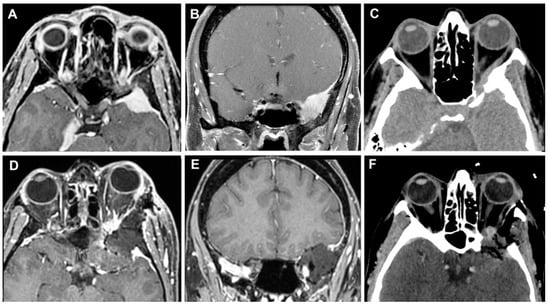

3.3. Clinical Cases

3.3.1. Case 1

3.3.2. Case 2